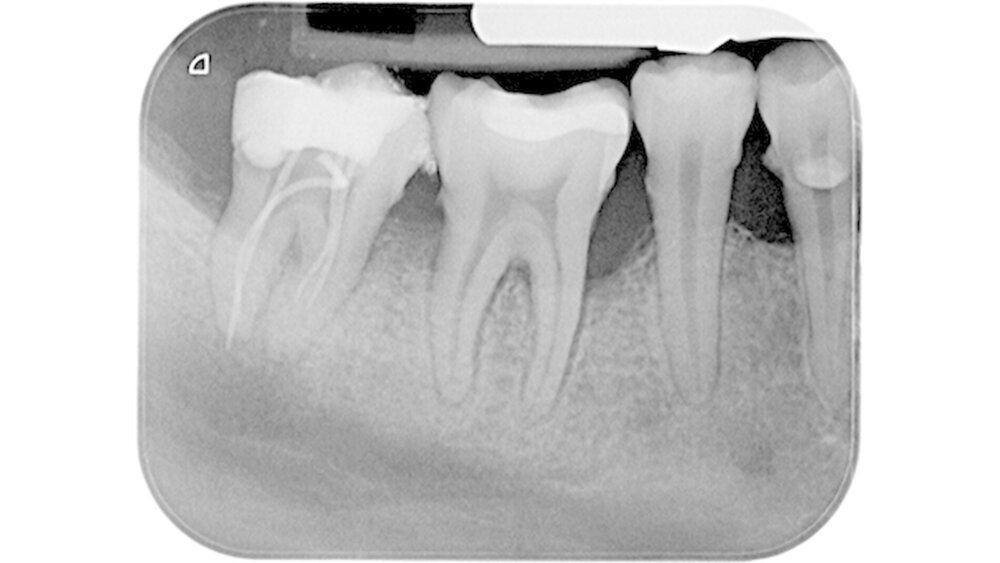

Die Aufnahme zeigte diesen Guttaperchapoint zwei Millimeter über den röntgenologischen Apex herausragen (Abbildung 1). Der Stift wurde wieder entfernt, eine Zwischeneinlage mit Calciumhydroxid appliziert und der Zahn temporär mit Glasionomerzement verschlossen. Die Patientin verließ die Klinik beschwerdefrei.

Der Zahn 47 stellte sich parodontal geschädigt und 1-gradig gelockert dar. Das Orthopantomogramm (OPTG) und der anschließend angefertigte Zahnfilm (Abbildungen 2 und 3) zeigten am Zahn 47 apikal weit überextrudiertes Wurzelfüllmaterial. Die Patientin wurde aufgrund der klinischen und der röntgenologischen Befunde sofort an die Klinik und Poliklinik für Mund-, Kiefer- und Gesichtschirurgie überwiesen.